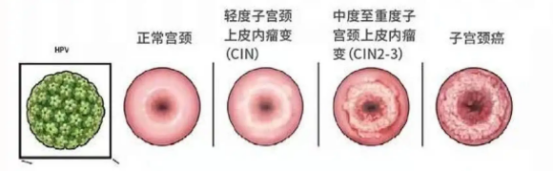

高危型HPV包含16、18、33、35、52、58型等,其中16、18、52、58型高达95%。之所以被叫做高危型,是因为它们具有致癌性,会引起宫颈癌、外阴癌、肛门癌等生殖道恶性肿瘤。感染HPV病毒必须提早治,更不能因为碍于面子逃避治疗,导致HPV疾病恶变!